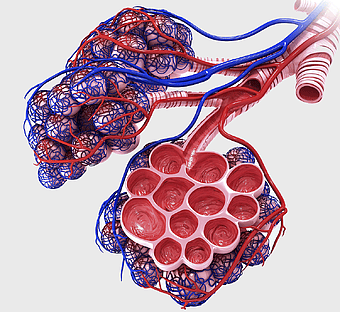

1159x1062px

human intestine illustration, Pulmonary alveolus Anatomy, Alveolar venous blood vessels, Bronchiole, respiratory system diagram, pulmonary circulation, lung vascular structure -

Respiratory system diagram, bronchiole structure, lung anatomy illustration, pulmonary alveolus function, respiratory health, breathing process visualization, trachea pathway -

lung anatomy, respiratory system illustration, pulmonary alveoli structure, trachea and bronchi, human lung function, diaphragm movement, breathing process diagram -